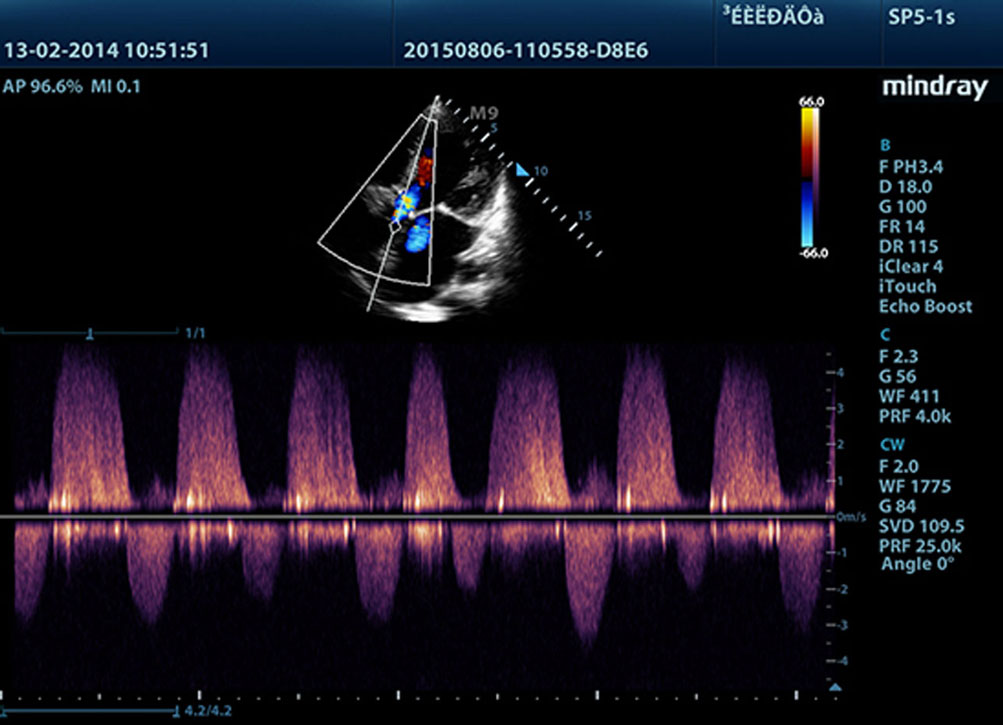

Fornendo immagini pi├╣ nitide, tutte le sonde compatibili con M9 sono dotate della tecnologia Mindray tecnologia trasduttore 3T, unica nel suo genere. Migliorato con l'aggiunta della tecnologia monocristallo, M9 offre una migliore penetrazione e un flusso dinamico del colore, in particolare durante la scansione di pazienti difficili.

LVO per ecocardiografia sotto stress

Le eccezionali capacit├Ā di M9 consentono lŌĆÖopacizzazione LV durante lo stress, migliorando distinzione tra tessuto miocardico e ristagno di sangue, fornendo una migliore visualizzazione della superficie endocardica. La funzione Stress Echo di M9 comprende un pacchetto completo per lo stress farmacologico e da sforzo. Il pacchetto ├© supportato da un sistema flessibile di rapporto che pu├▓ essere ottimizzato sulle esigenze individuali.